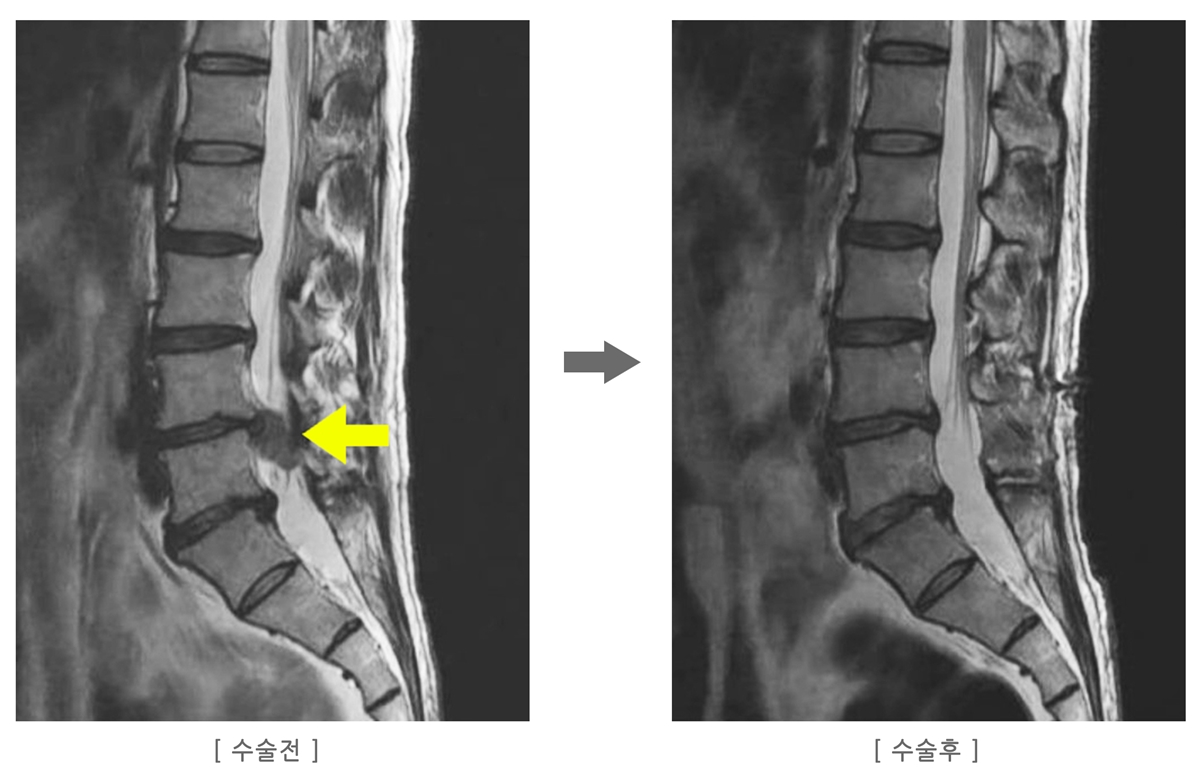

└ 지금 내 통증이 단순 근육통인지, 디스크 위험 단계인지 1~5단계 체크리스트로 구분합니다. - 2편. 허리디스크 수술 전 MRI 판독법, 초보자 가이드

└ L4-L5, L5-S1 같은 용어와 ‘돌출·탈출·신경 압박’ 표현을 쉽게 풀어서 설명합니다. - 3편. 허리디스크 수술비·보험·지원금 실전 정리